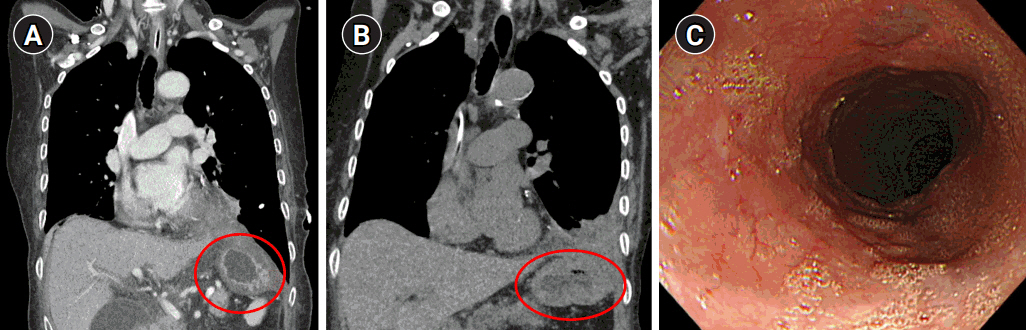

After general anesthesia, laparoscopic exploration (as shown in the video) confirmed that the stomach and transverse colon had been herniated into the thoracic cavity. The ports were positioned similar to those of laparoscopic gastrectomy, but with the operator’s ports placed slightly more medial and upwards (Fig. 2) considering the left-sidedness of the diaphragmatic hernia. Had the diaphragmatic hernia been right-sided, the author would have placed the ports slightly more lateral and lower. Using laparoscopic graspers, the stomach and transverse colon were carefully pulled back into the abdominal cavity (Fig. 3A). Adhesions around the stomach, which were severe most likely due to the chronic herniation, were carefully dissected using a laparoscopic electrode device (Fig. 3B). After meticulous dissection, the stomach was finally mobilized from the thorax and successfully pulled back into the abdominal cavity. Hernia sac was then meticulously dissected, allowing the esophagus to be identified (Fig. 3C). During this procedure, the distal esophagus was injured, creating an iatrogenic hole, which was repaired using 3-0 continuous absorbable barbed suture (Monofix®; Hanmi Healthcare) (Fig. 4). Endoscopic stent or endo-vac therapy, which have been reported to be effective in treating esophageal perforations after paraesophageal hernia operations, was planned to be used postoperatively if necessary [4,5].

Following surgery, the patient underwent endo-vac therapy and endoscopic stent insertion due to leakage from the esophageal injury site. After approximately three months of nutritional support and conservative care, follow-up CT and EGD showed that there was no herniation and that the perforation site had been sealed with no signs of fistula (Fig. 6).

Fig. 2.Laparoscopic port positions. The typical gastrectomy ports are shown in green, while red shows the author’s preferred positions for left-sided diaphragmatic hernia and blue represents the positions for right-sided diaphragmatic hernia.

Fig. 5.Biomesh repair procedure. (A) Evaluation of the herniated space after reduction (circle). (B) 360° continuous suture fixation of the biomesh to the diaphragm (dotted arrow line). (C) Confirmation of repair.

Fig. 6.Follow-up computed tomography at postoperative day 17 (A) and 3 months (B), showing no herniation of the stomach and bowel contents (circles). (C) Esophagogastroduodenoscopy finding at postoperative 3 months, showing no clear trace of the previous perforation site.